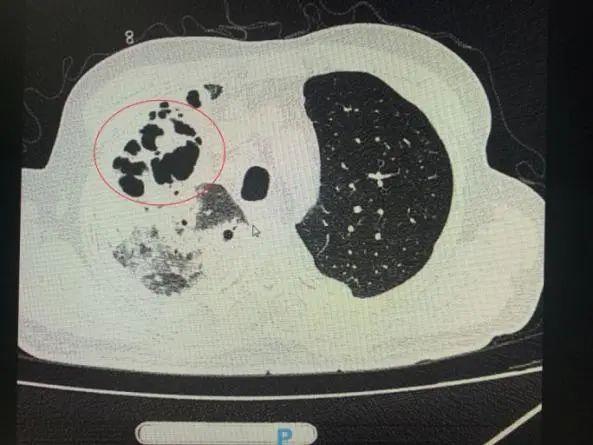

番禺院區(qū)呼吸內(nèi)科何夢(mèng)璋主任接診后,對(duì)鐘叔進(jìn)行詳細(xì)檢查。此時(shí),鐘叔的病情已經(jīng)十分危急,由于不能自主呼吸,他帶上了呼吸機(jī)輔助呼吸調(diào)節(jié)。看到鐘叔胸片時(shí),醫(yī)護(hù)人員頭皮也一陣發(fā)麻,胸部CT可見(jiàn)雙肺多發(fā)的炎癥浸潤(rùn)、雙肺多發(fā)空洞。通俗來(lái)說(shuō),鐘叔的肺部已經(jīng)被病原體蠶食,啃出個(gè)大小各異的洞!可怕的是,這種病變對(duì)肺功能的破壞是性、不可恢復(fù)的。根據(jù)鐘叔病史以及胸部CT結(jié)果,終診斷為“吸入性肺膿腫”。

鐘叔的肺部被病原體蠶食,啃出個(gè)大小各異的洞。